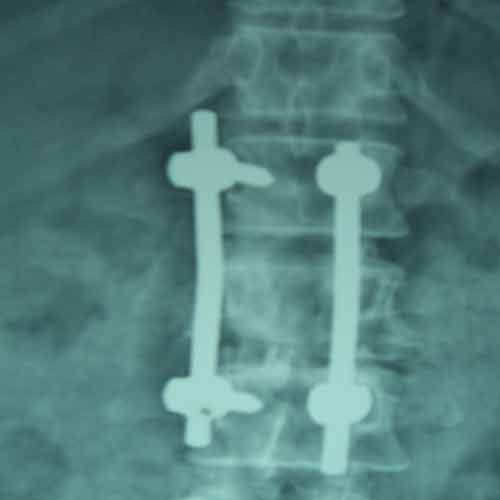

Case:2 Traumatic Fracture L2 with Cauda Equina

Male 65 years of age presented with 1 month old fracture L2 with paraparesis & bladder, bowel involvement. He was treated with Laminectomy (Decompression) & fixation with pedicular screws neurological full recovery by 10 days post-operative.

Post-opAp